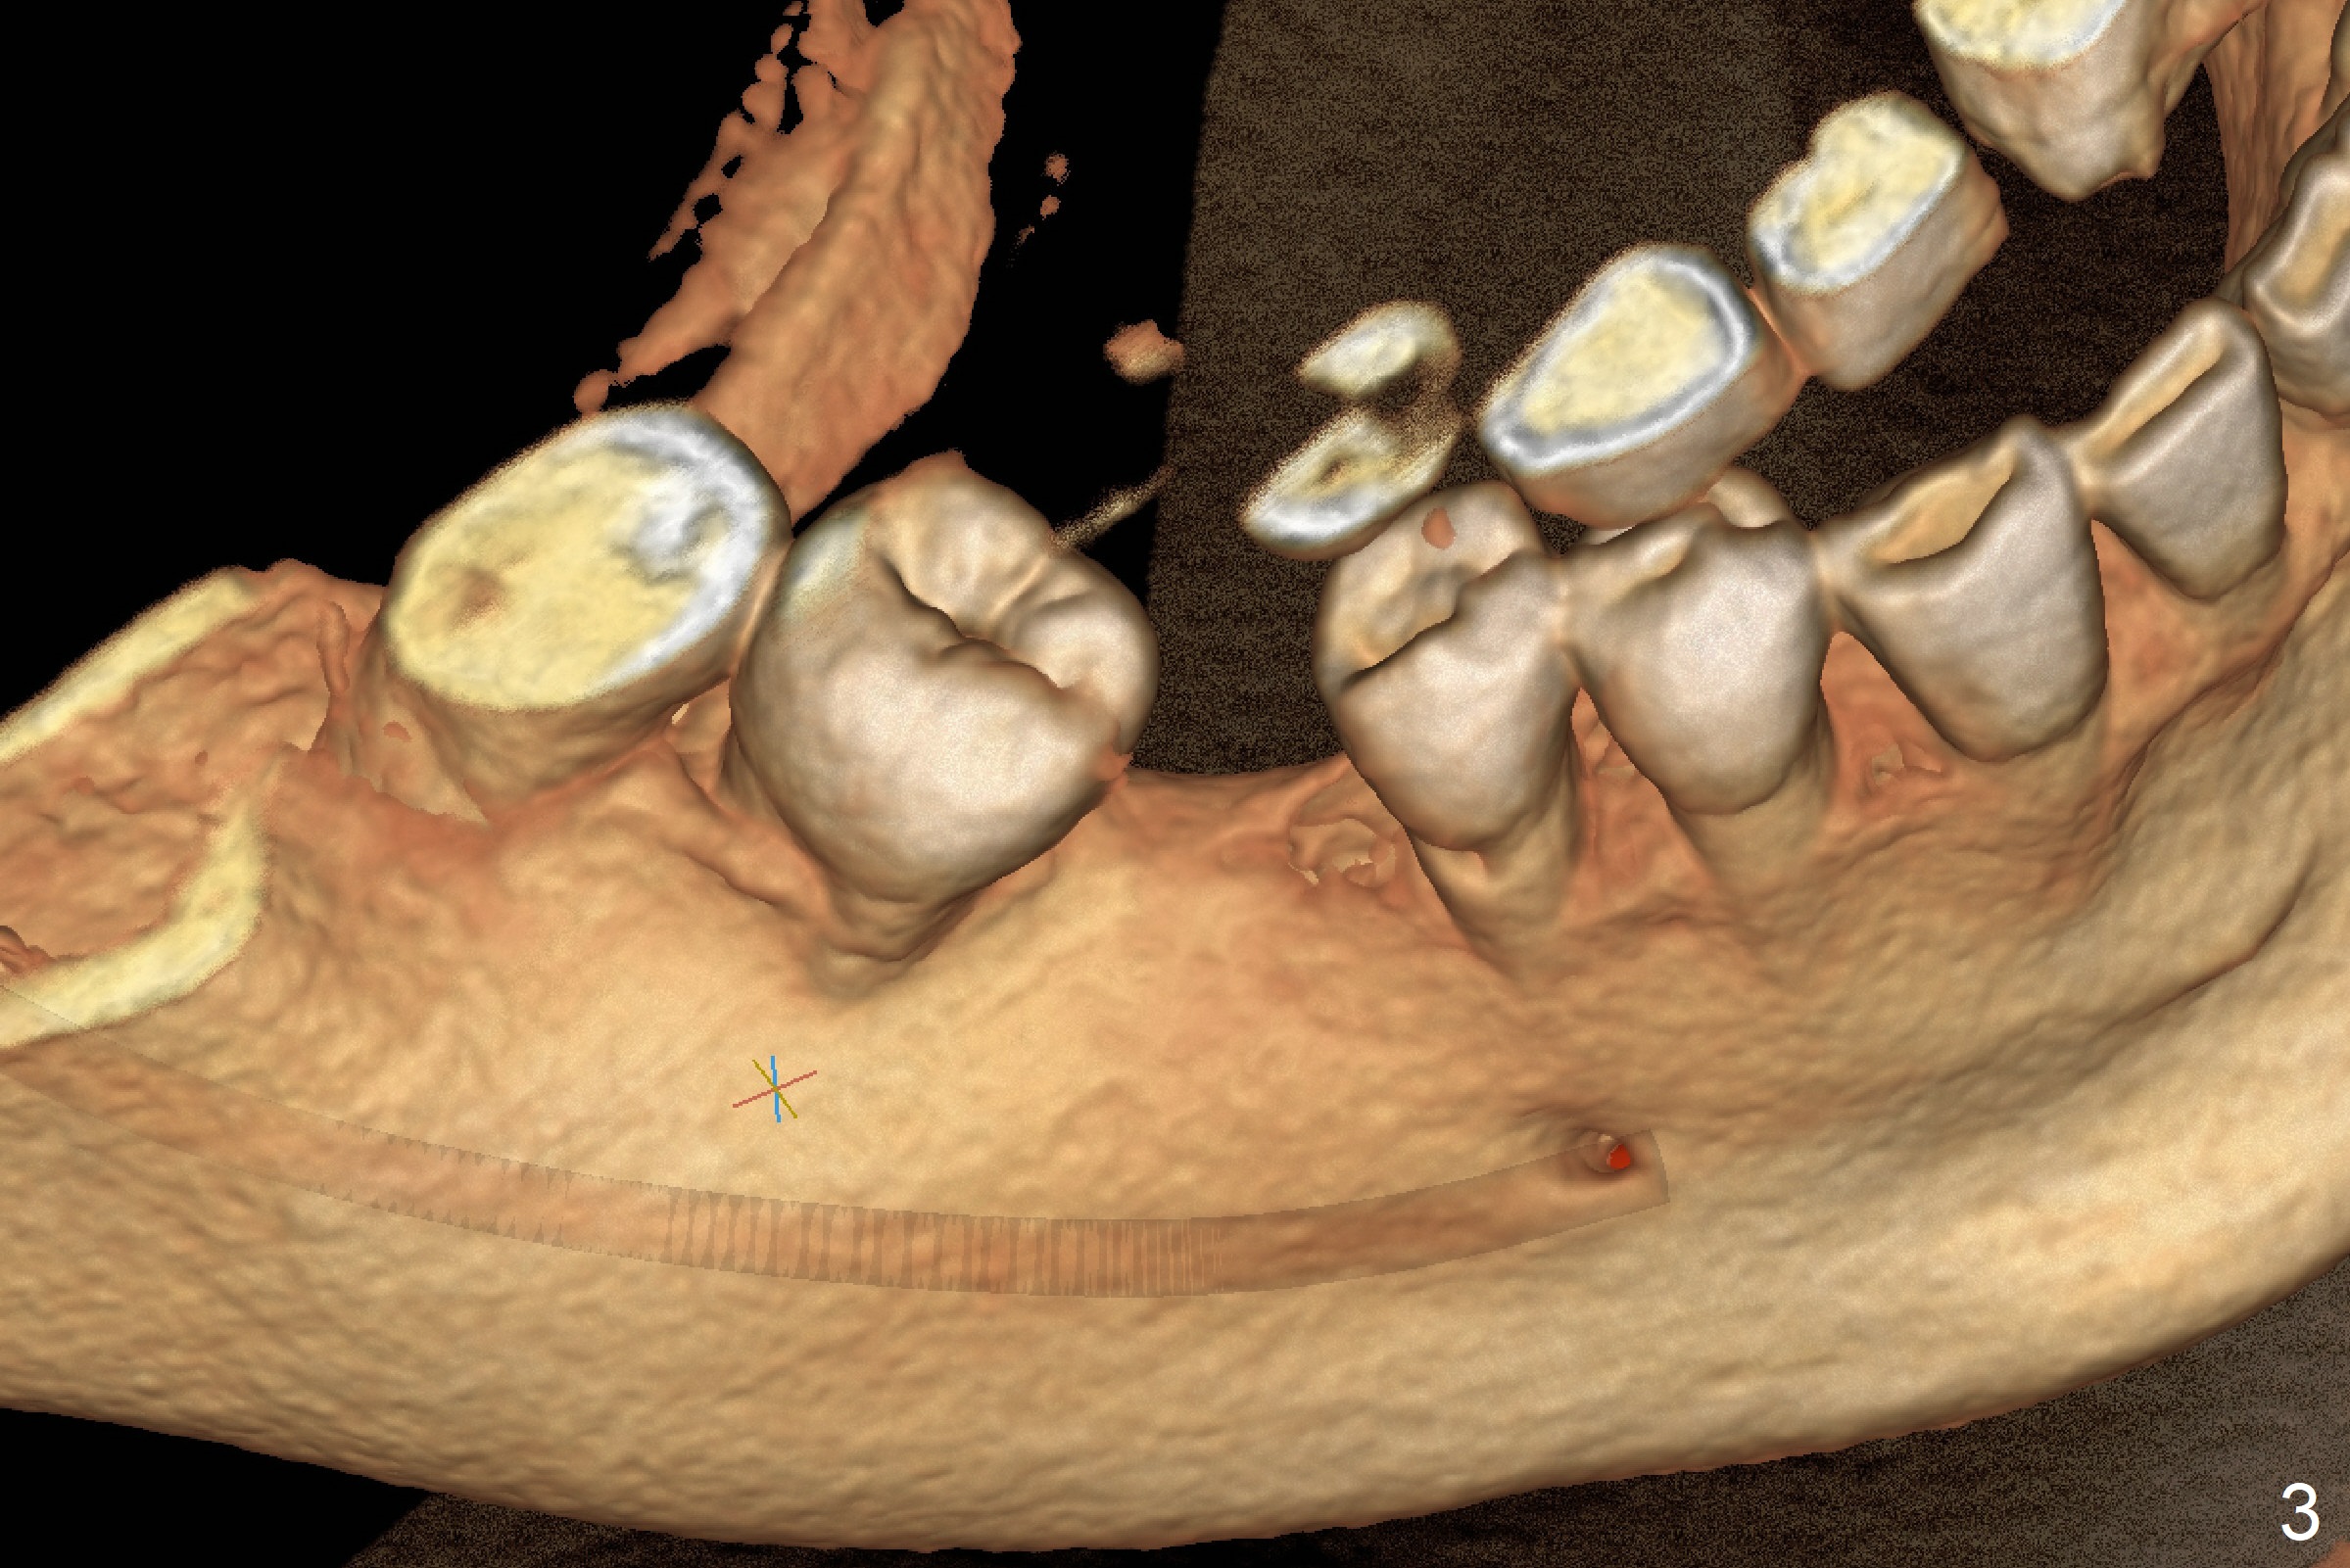

2.5 mm Implant at 1st Molar A 45-year-old woman requests an implant at #30 immediately post #3 implant cementation (Fig.1). She is reluctant to have #32 extraction for ortho. After trimming #29 distal and #31 mesial surfaces, a 2.5x12 mm implant will be placed using a tissue punch in the kit (Fig.2,3). Prepare the Regular and Basic Implant Cassettes. Return to

Lower

Molar Immediate Implant, Armaments Xin Wei, DDS, PhD, MS 1st edition 05/23/2018, last revision 06/01/2018 |